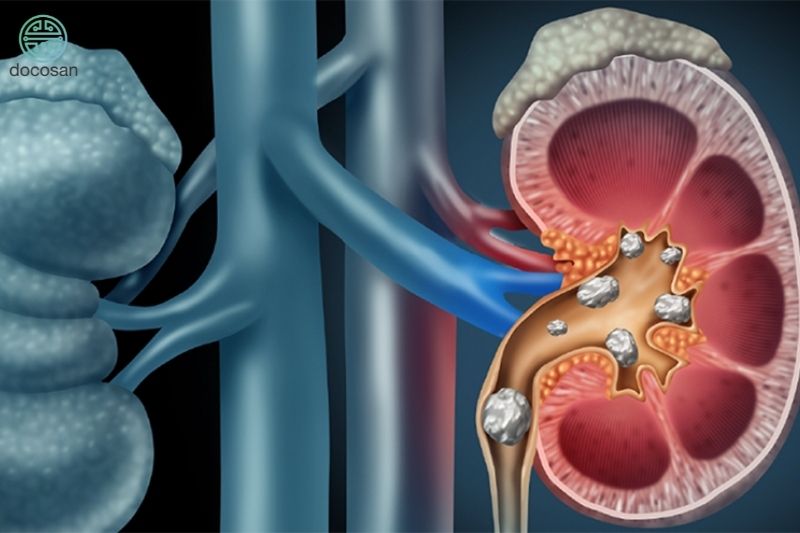

Bệnh thận ứ nước được chia làm 4 mức độ chính, trong đó bệnh thận ứ nước độ 4 là giai đoạn nghiêm trọng nhất của bệnh. Khi đó, nước ứ đọng trong thận thời gian dài khiến cho thận dãn nở quá mức, sưng to và biến dạng. Do đó có thể dẫn đến các biến chứng nguy hiểm như tổn thương thận, mất chức năng thận, vỡ thận. Điều này khiến bệnh nhân phải chịu những cơn đau dữ dỗi mỗi ngày, không những thế thận ứ nước độ 4 có thể ảnh hưởng đến tính mạng của người bệnh.

Thận ứ nước độ 4 xuất hiện sự giãn nở của đài thận là rất lớn, có thể lên đến trên 20mm với biểu hiện đau phần hông lưng nghiêm trọng và thường là than phiên chính của bệnh nhân khi nhập viện. Để xác định chính xác xem bạn có đang bị thận ứ nước không và bệnh đang ở mức độ nào, một số xét nghiệm cần phải thực hiện bao gồm: xét nghiệm nước tiểu, xét nghiệm máu và chẩn đoán thông qua hình ảnh chụp CT, X-quang.

Các nguyên nhân ít phổ biến hơn của thận ứ nước bao gồm sỏi thận, khối u ở bụng hoặc xương chậu và các vấn đề với dây thần kinh bàng quang.